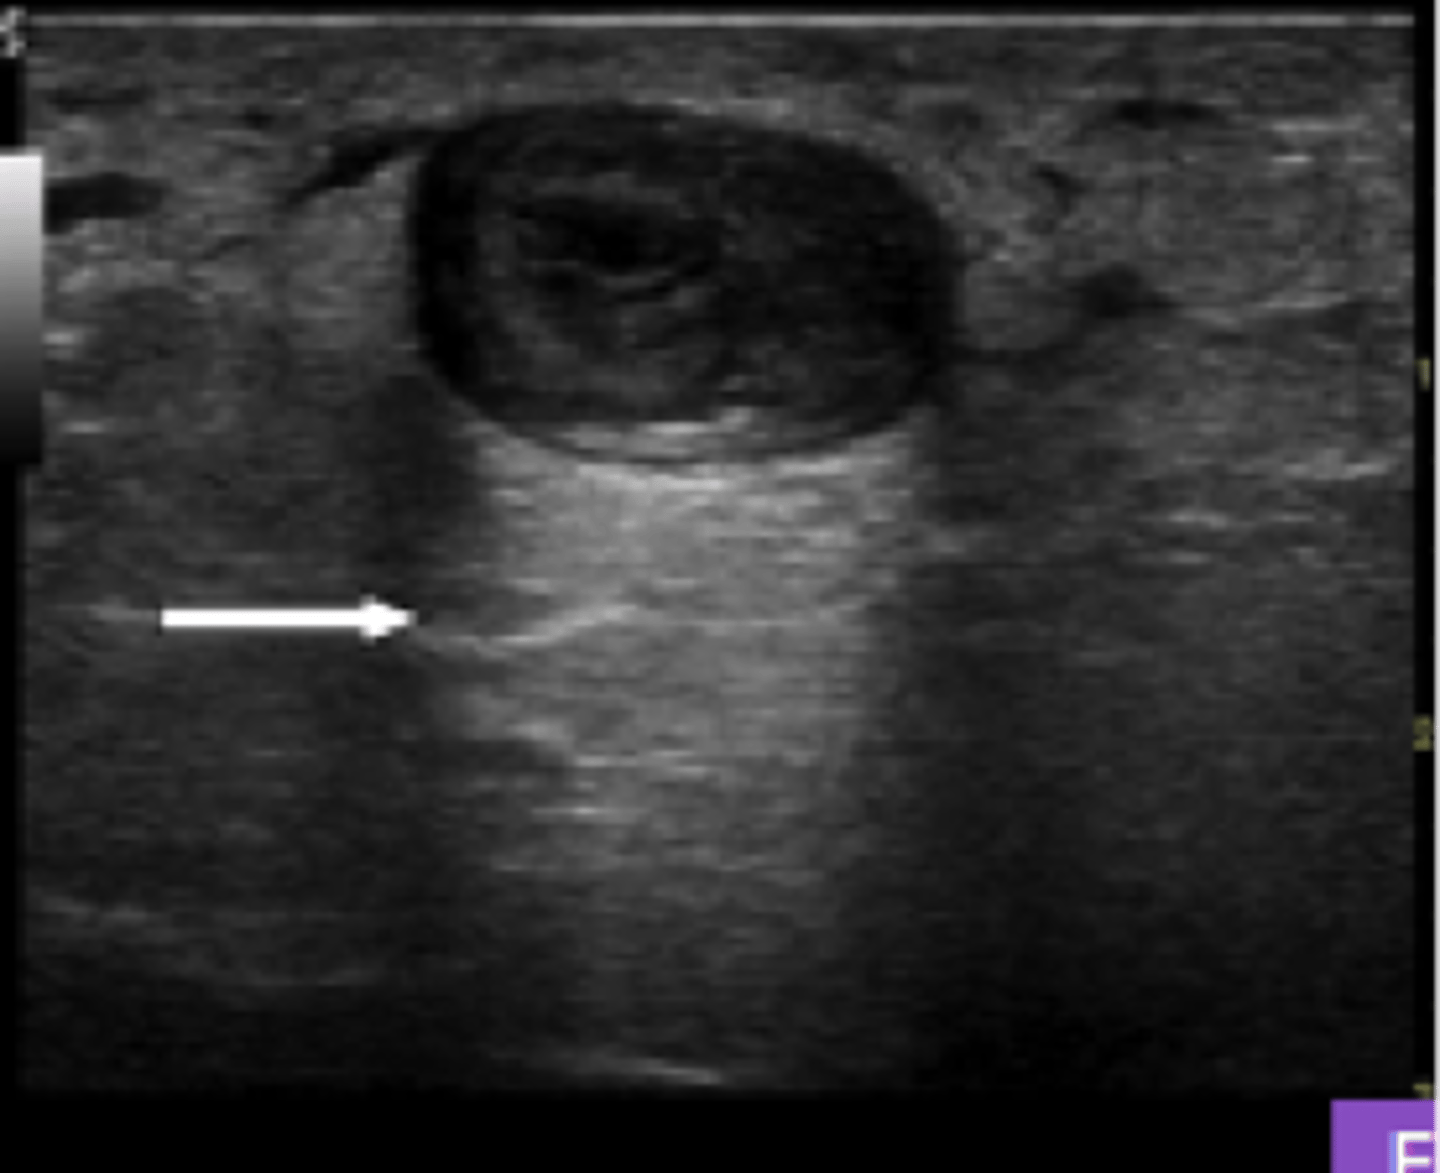

What ultrasound artifact cannot be seen below a structure so reflects back ALL waves?

Acoustic Shadow

ex. ribs

What ultrasound artifact causes (artificial) brightness DEEP to an anechoic structure?

Acoustic Enhancement